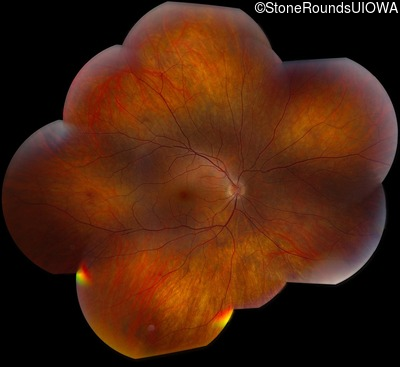

AD CSNB (IA2fii)

AD CSNB (IA2fii)

History

This 44 year old woman has had very poor vision in dim light for her entire life. She vividly remembers running into a picnic table on a bicycle in a campground as a child.